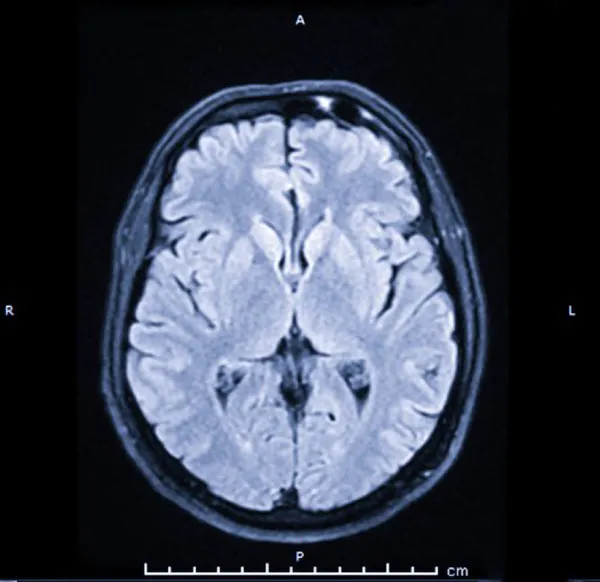

Şok edici röntgen görüntüleri, 3,2 cm büyüklüğündeki çivinin, hareket ve konuşma için hayati önem taşıyan beyninin ön lobunun derinliklerine saplandığını gösteriyordu. Üstelik kanama beyninin diğer bölgelerine yayılmıştı.